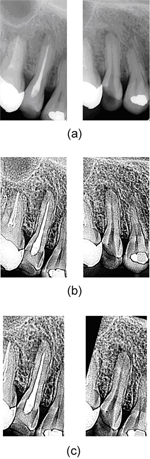

歯のエックス線写真は、撮影のタイミングによりエックス線照射量が異なるため、ぼけてしまうことが多いです。診療には問題ありませんが、コンピュータで処理をするときには、このようなぼけにより画像処理の精度が下がってしまいます。そこで、前処理として画像のコントラストを強調します。図2の(b)がコントラスを強調した例になります。

(a)正確に類似度を求めるためには、正確かつ高精度に画像間の拡大縮小と回転、平行移動を補正する必要があります。開発したシステムでは、位相限定相関法を用いて、正確に補正しています。図2の(c)が位置を合わせた結果になります。

【図2】歯のエックス線写真の位置合わせ:

(a)入力画像(左)と

データベースに格納されている登録画像(右)

(b)コントラストを強調した画像

(c)位置や角度を補正した後の画像

【図3】歯のエックス線写真のひずみ補正:

(a)左の画像にある基準点に対応する点を右の画像から求めた結果

(b)得られた対応関係より作成したひずみモデル

(c)ひずみ補正後の画像

(b)画像間のひずみを補正します。撮影のたびに、エックス線の照射角度とフィルムの角度が異なってしまうため、画像間にひずみ(歯が伸びたり縮んだりすること)が生じてしまいます。ひずみが生じていると、同じ歯を撮影したとしても長さが異なってしまうので、誤って違う人の歯と判断してしまいます。そのために、識別精度が著しく低下してしまう恐れがあります。そこで、画像を小さなブロックに分け、位相限定相関法を利用してブロック間の対応関係を求め、その関係から得られる情報を用いてひずみを補正します。図3がひずみ補正の様子になります。

以上の処理により位置や角度、ひずみを補正し、共通領域を求めた例が図3の(c)になります。どれくらい正確に位置合わせされているかを調べるために、図4のように位置合わせした画像の差をとってみました。画像がきれいに重なっているので、治療した部分がはっきりと表れています。

(a)ひずみ補正をした後の画像

(b)重ね合わせた結果